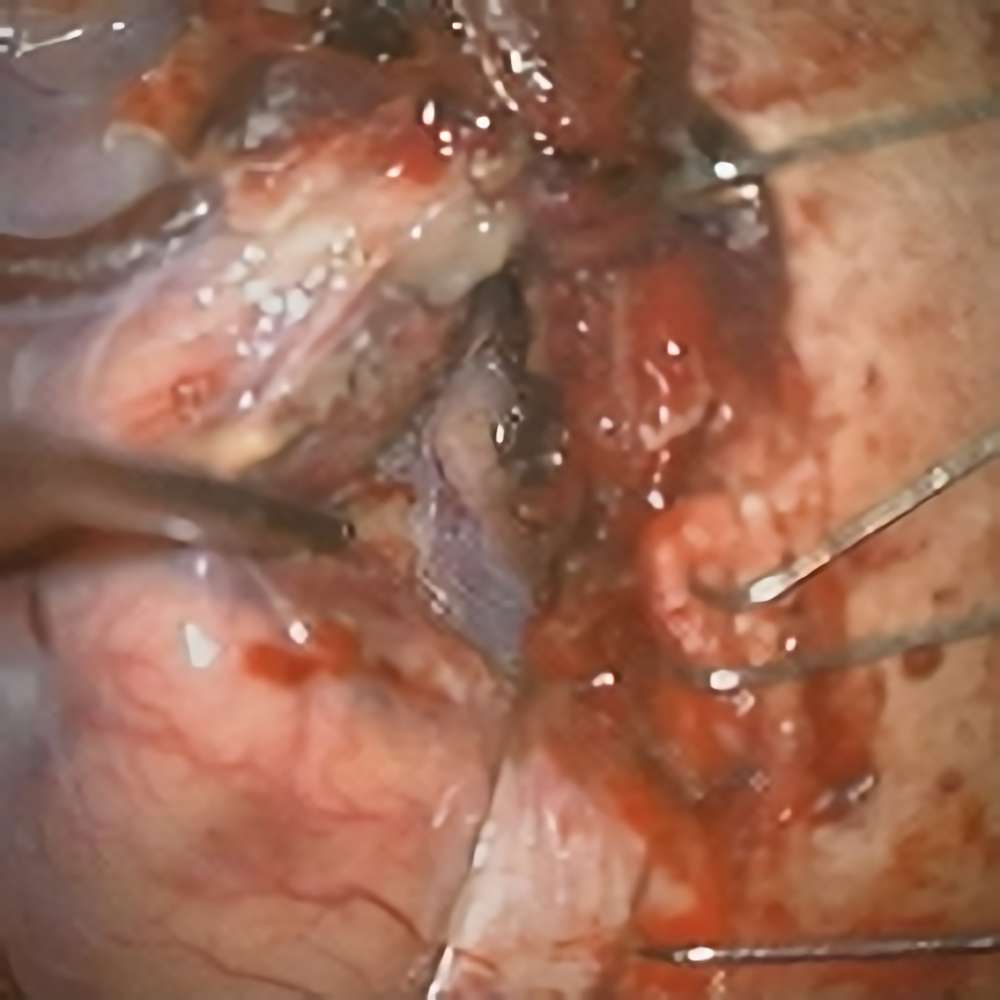

285

'22年4月

70代

膠芽腫

頭蓋内腫瘍摘出術

No.’22_42 手術前1

No.’22_42 手術前2

No.’22_42 摘出 前

No.’22_42  摘出 中

No.’22_42 摘出 後